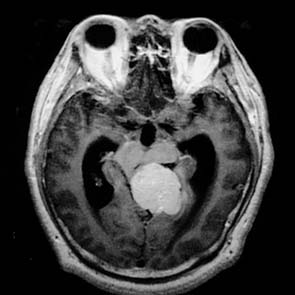

2.CT及MRI掃描 腫瘤體積一般較大(多大於3.5cm)位於橋小腦角,以廣基與岩骨相連邊界清楚,呈卵圓形,基底附著寬。不增強時密度鶒不高,均勻一致,注射造影劑後呈均一性強化。可見鈣化或岩骨骨質破壞或增生。腫瘤不以內聽道口為中心,內聽道一般不擴大,而往往與小腦幕有粘連,冠狀掃描更能證實腫瘤與小腦幕的關係。在MRI圖像中,腫瘤信號與腦灰質相似,T1加權像上為低、等信號,T2加權像上為等、高信號;瘤內可見鈣化或囊變,腫瘤周圍多伴有水腫。腫瘤與周圍的關係顯示更加清晰,這對制訂手術方案是極為有利的。